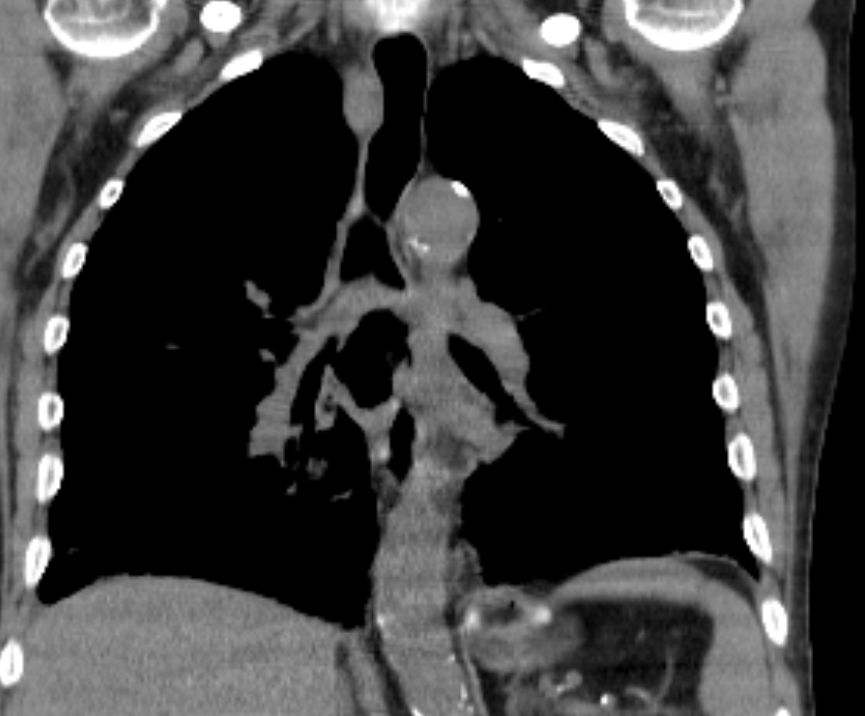

CT Infiltration des oberen Mediastinums. Flottierender Thrombus in der Vena cava superior.